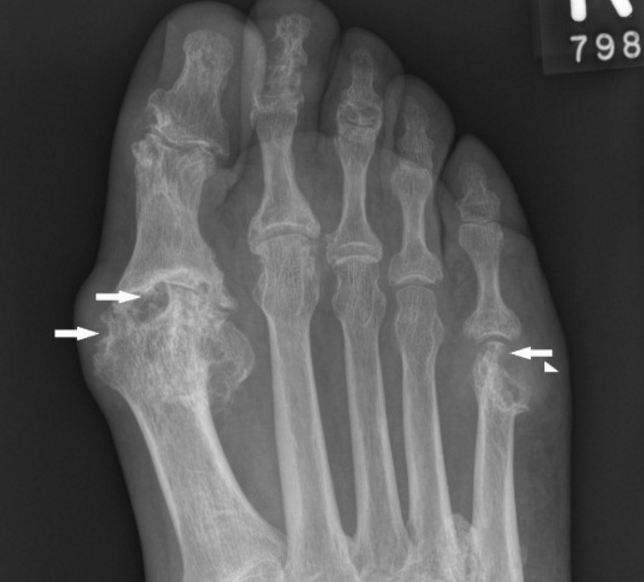

Joint point

Joint point 136 фотографий